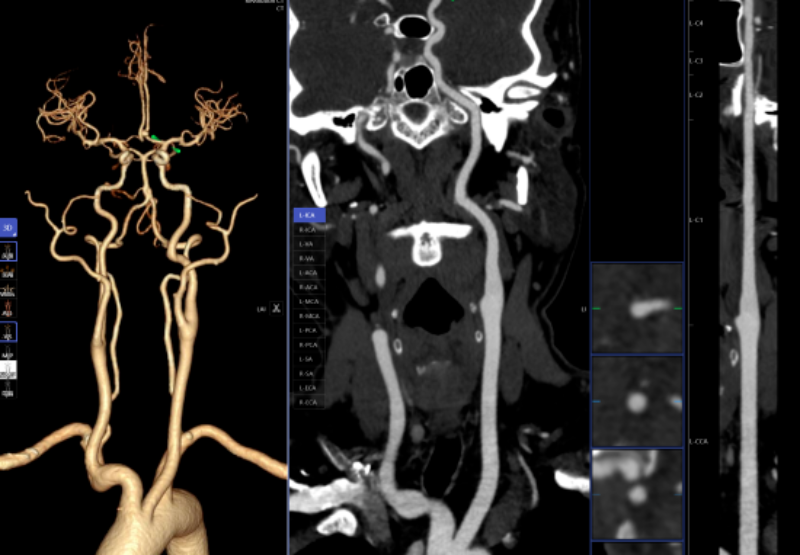

血管诊断、脑血管灌注成像

头颈部CTA、冠状动脉CTA、肺动脉CTA及肢体CTA是一种无创、低风险、快速的检查方法,能够清晰识别血管狭窄、畸形或斑块,明确病灶与周围正常组织的位置关系,为治疗方案的制定提供有力依据,能提高患者生存率,缩短高危患者急救救治时间。

以往,放射科医生进行头颈部CTA和冠状动脉CTA重建后处理,需要医生应用工作站手动处理,耗时约20-30分钟。而AI人工智能辅助诊断系统通过计算机视觉和深度学习技术,仅需5-10分钟即可完成影像重建的后处理计算,一键生成精准的三维重建图;系统还能自动标记血管名称、快速判断斑块性质,并根据最新指南对狭窄程度进行分级诊断等,帮助医生快速定位病变节段,准确分析斑块类型及狭窄程度;对脑血管灌注成像进行快速重建和诊断,大幅缩短患者等候检查和获取诊断报告的时间。